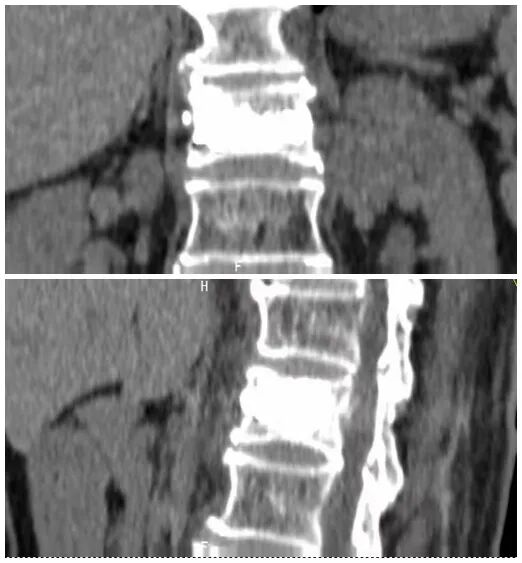

术前磁共振检查提示腰1椎体新鲜压缩性骨折

术后复查CT可见骨水泥弥散充分